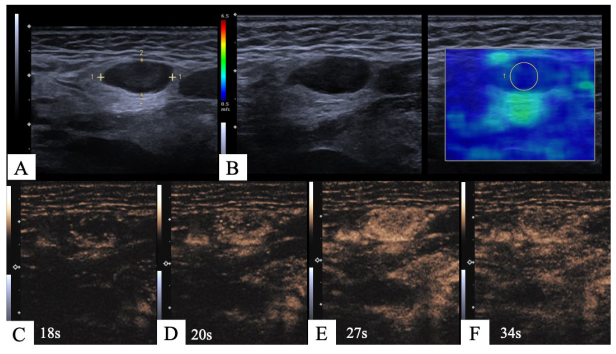

2.2. Imaging Protocol

2.3. Image Interpretation